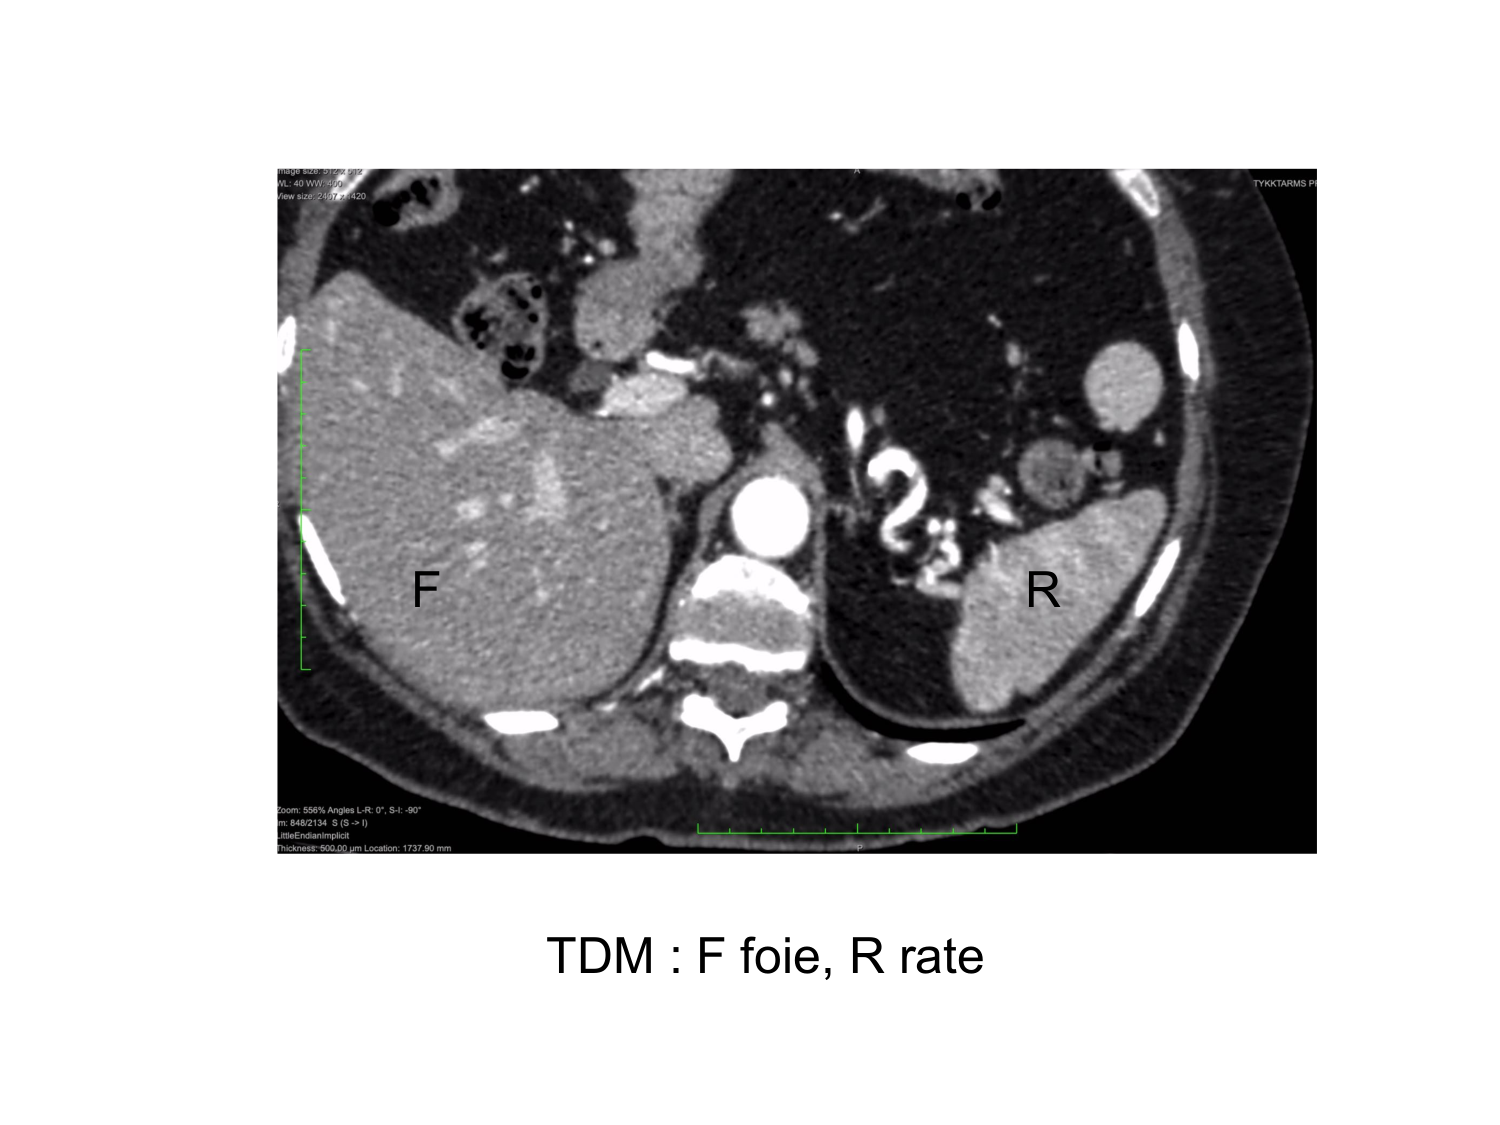

11.35 · Abdomen gros intestin foie rate pancreas vascularisation

Abdomen gros intestin foie rate pancreas vascularisation